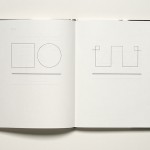

// The Alzheimer disease moves itself slowly, silently, almost unnoticed. As a mold it expands within the Brain. Bit by bit, invisible, creeping, it conquers and controls the body and soul of many human beings. The Book “Demens” is the attempt to effectively communicate what Alzheimer causes. The visualization is composed by emotional abstract pictures, practical information as well as diagnostics tests and quotes from several Alzheimer patients.

// Die Alzheimer-Krankheit bewegt sich anfangs leise, fast unbemerkt. Wie ein Schimmel breitet sie sich im Gehirn aus. Stück für Stück, still, schleichend, aber zielstrebig erobert und steuert sie den Körper und Geist vieler Menschen. Das Buch »Demens« verkörpert den Versuch, die Alzheimer Krankheit objektiv, ausführlich und verständlich zu vermitteln. Zur Visualisierung dieser Krankheit werden emotionale und abstrakte Bilder, objektive und praktische Informationen sowie aus¬gewählte Diagnose-Verfahren und Zitate einiger Alzheimerkranker zusammengefügt.